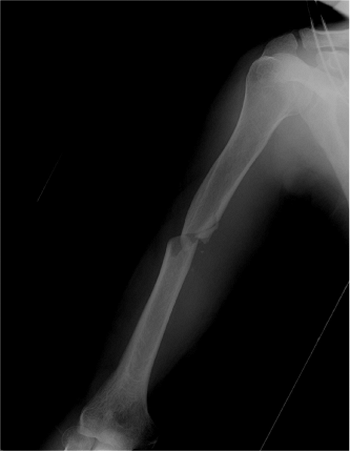

endotracheal tube brought out toward the side opposite the humeral

fracture. Preoperative antibiotics are given. Injury radiographs are

available in the operating room (Fig. 6.14).

Figure 6.14. Preoperative AP radiograph before antegrade humeral nailing.